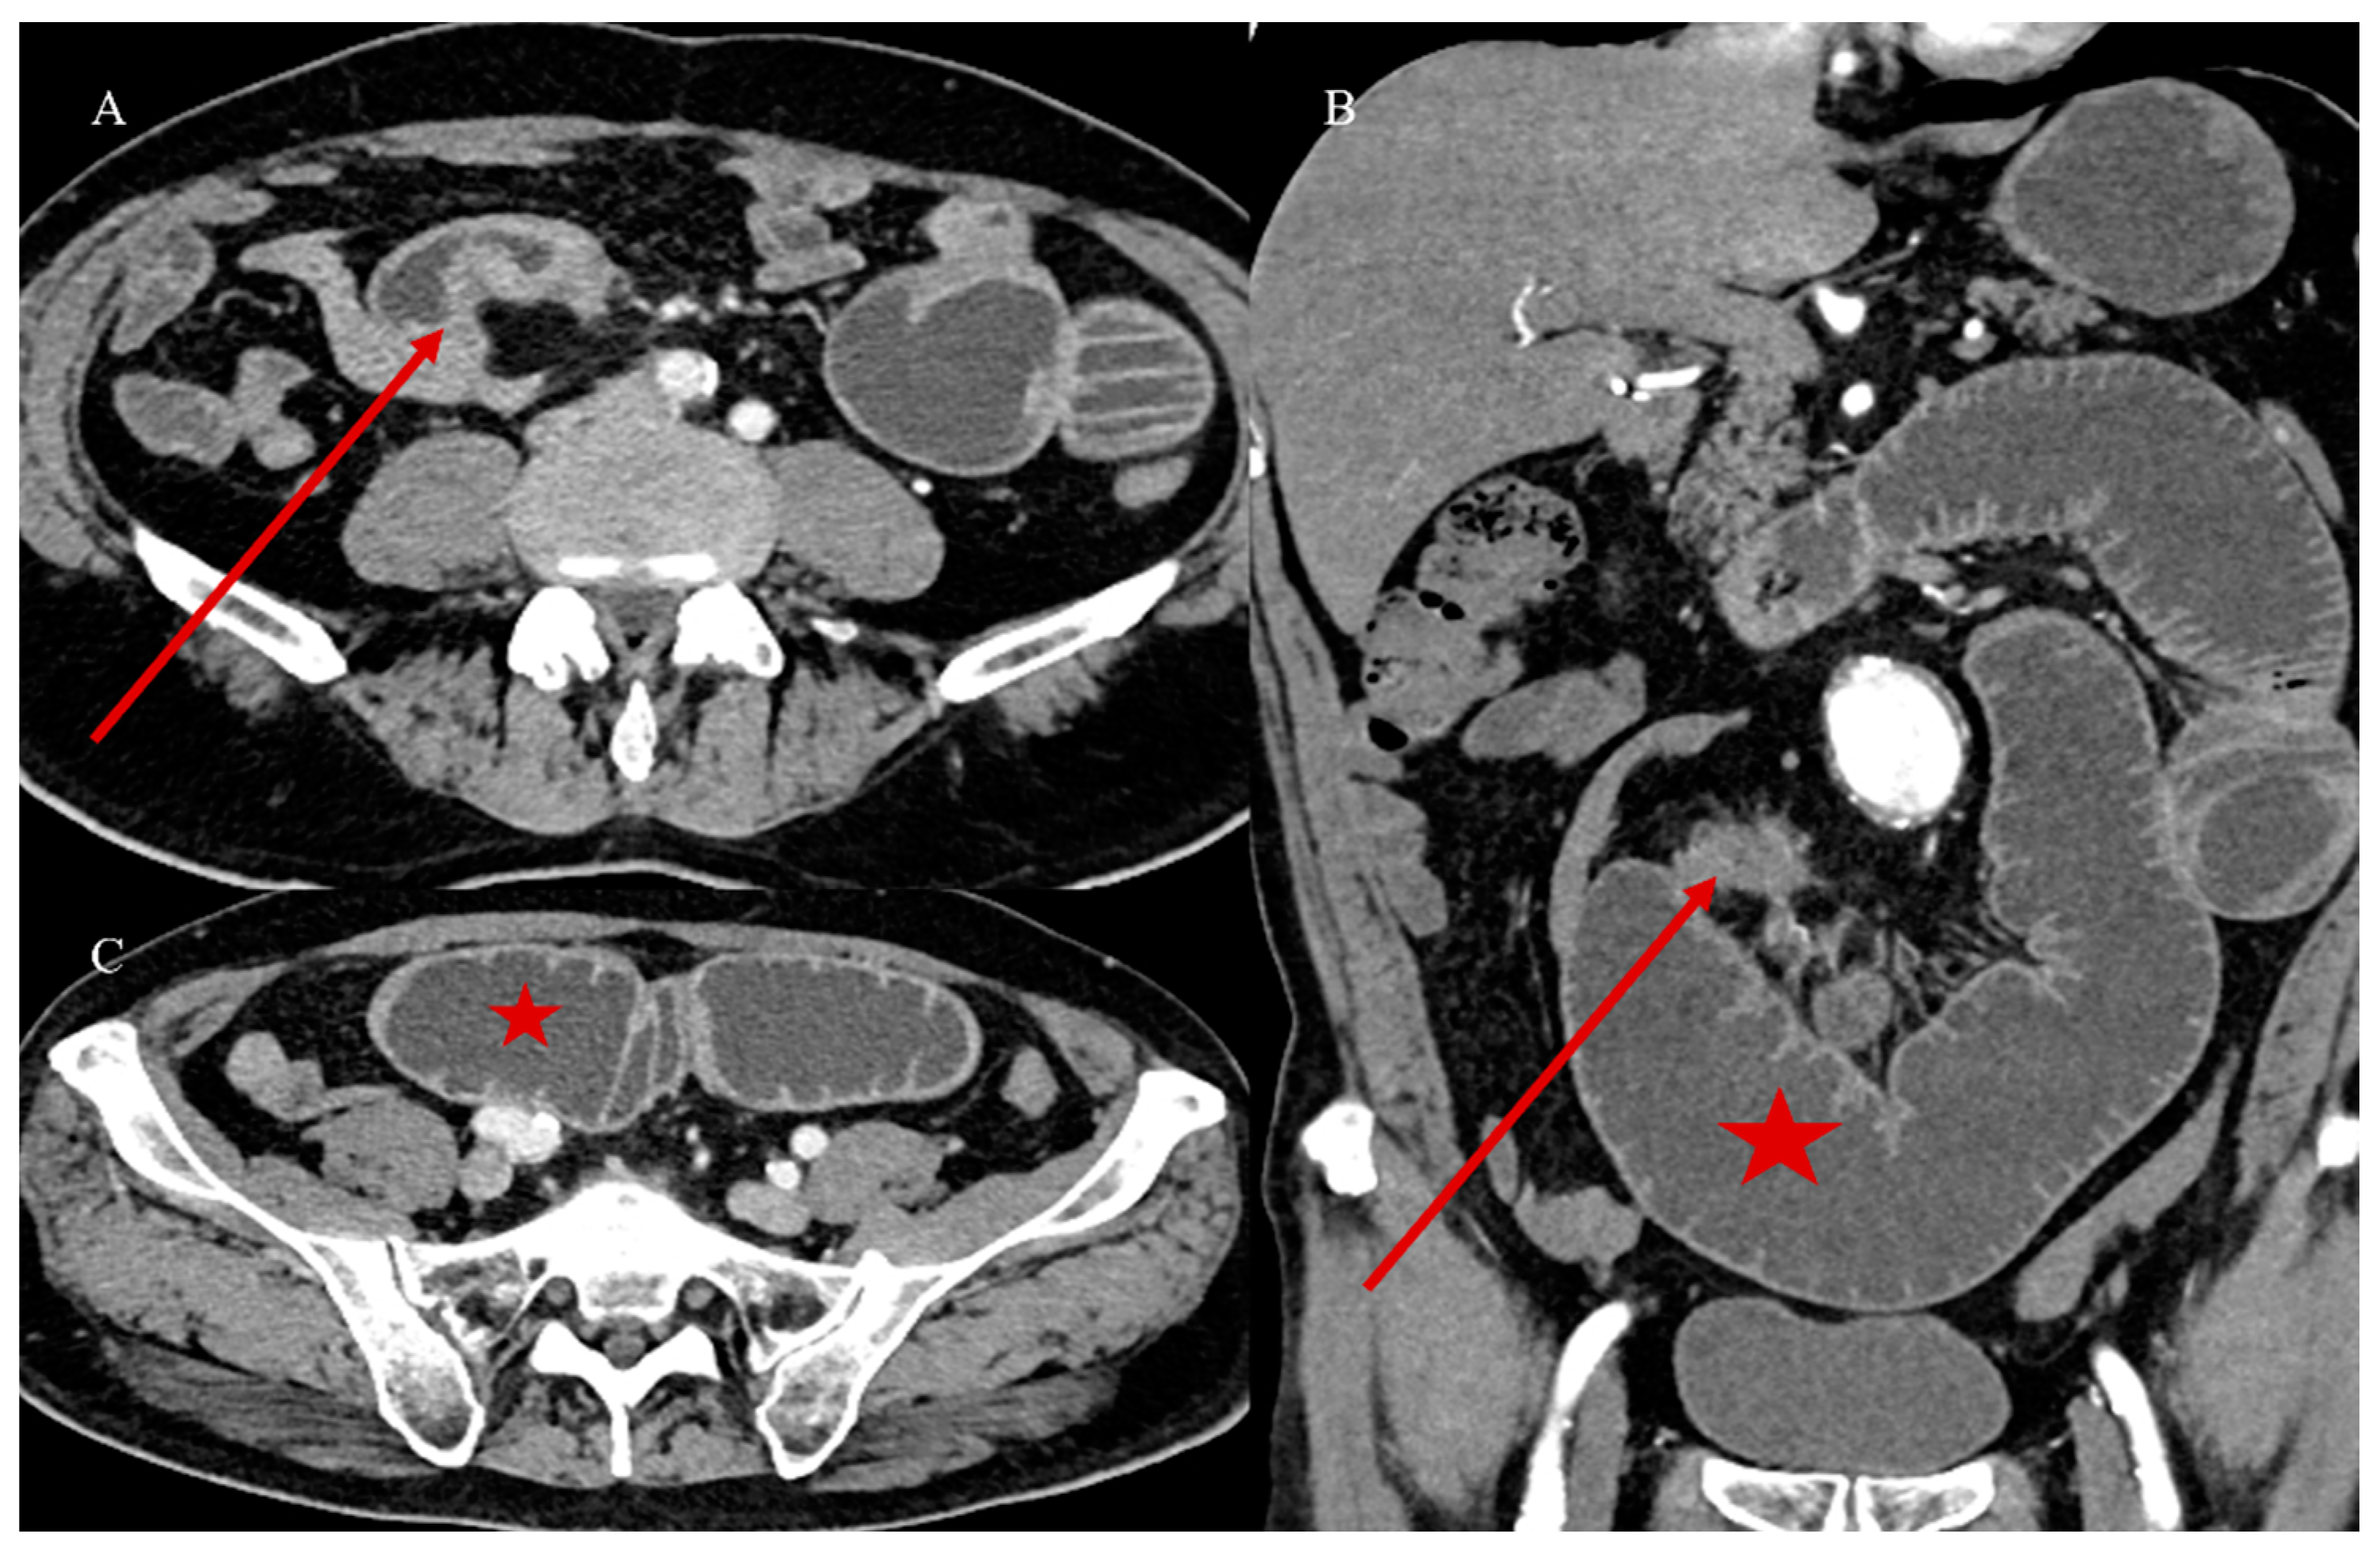

- Bonomi, A.; Romario, U.F.; Funicelli, L.; Conti, G.; Luc, M.R.; Ceci, F.; Pozzi, S.; Radice, D.; Fazio, N.; Bertani, E. Diagnosis and staging of small intestinal neuroendocrine tumors with CT enterography and PET with Gallium-68: Preoperative risk stratification protocol. Langenbecks Arch. Surg. 2024, 409, 63. [Google Scholar] [CrossRef]